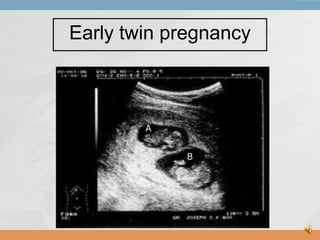

Ultrasound of Fetus

Early twin pregnancy